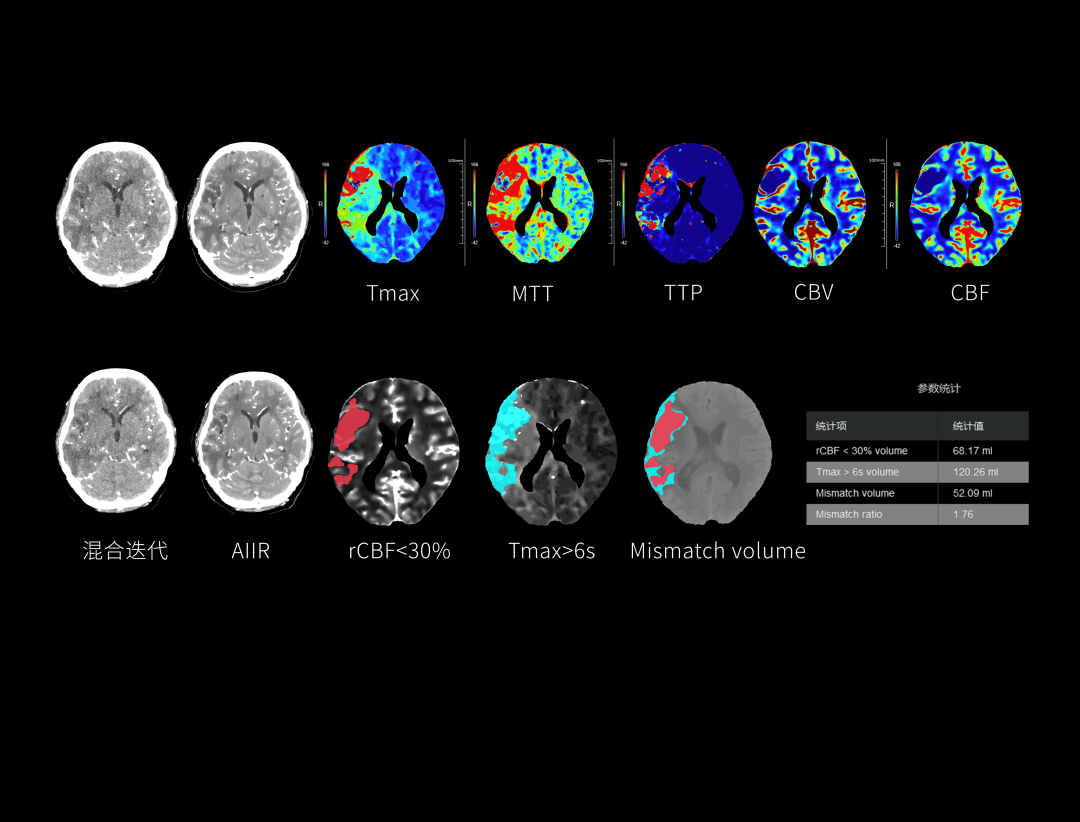

AIIR图像重建提升结果图像可解释性与算法鲁棒性,获得低剂量下的高清成像,超越传统,引领CT成像新标准